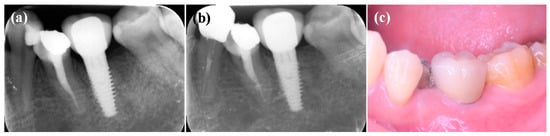

Similar findings were also observed in other patients with the IDCT-modified Ti implant treatment. The follow-up after four months showed a radiologically and clinically health condition reflected by no further bone loss found around the dental implant (Figure 7 and Figure 8).

Figure 8.

The radiographic images taken from the left mandibular premolar with the IDCT-modified Ti implant after (a) one-month placement, (b) four months placement, and (c) clinical evaluation (four months placement).